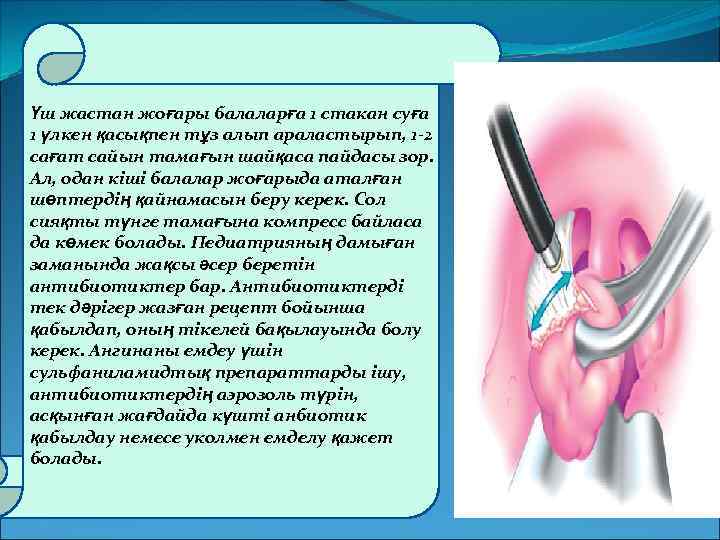

Үш жастан жоғары балаларға 1 стакан суға 1 үлкен қасықпен тұз алып араластырып, 1 -2 сағат сайын тамағын шайқаса пайдасы зор. Ал, одан кіші балалар жоғарыда аталған шөптердің қайнамасын беру керек. Сол сияқты түнге тамағына компресс байласа да көмек болады. Педиатрияның дамыған заманында жақсы әсер беретін антибиотиктер бар. Антибиотиктерді тек дәрігер жазған рецепт бойынша қабылдап, оның тікелей бақылауында болу керек. Ангинаны емдеу үшін сульфаниламидтық препараттарды ішу, антибиотиктердің аэрозоль түрін, асқынған жағдайда күшті анбиотик қабылдау немесе уколмен емделу қажет болады.